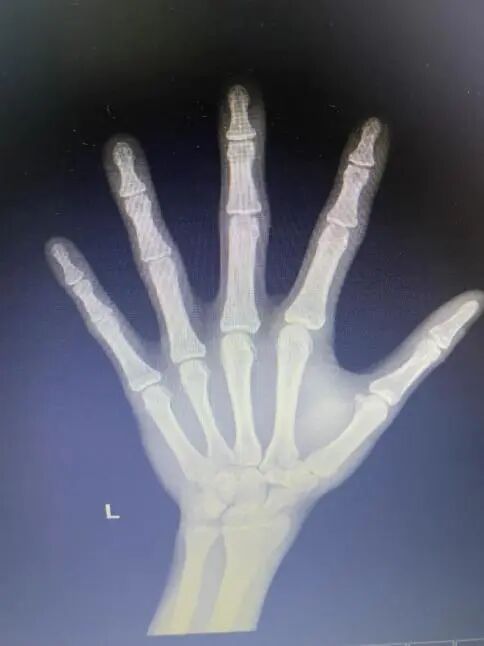

陳女士說:“我女兒今年13歲,但是近兩年沒怎么長高,去年大概長了1cm,現(xiàn)在身高145cm。幾個月前,我女兒自己在網上查了如何才能長高,硬要我?guī)メt(yī)院拍骨齡,看看還能長多高。我?guī)牧斯驱g,醫(yī)生說孩子的骨骺已經閉合了,再也沒機會長高了。我就想問問,真的一點機會都沒有了嗎?”

我詢問了紅紅的一些基本情況,又看了孩子的骨齡片,雖然有些殘忍,但還是跟家長說明:“骨齡已經閉合,確實沒什么長高空間了?!拔蚁乱庾R地問:“你女兒對身高很在意嗎?”

孩子現(xiàn)在剛好13歲,身高145cm,體重35kg,11歲半時出現(xiàn)月經初潮,當時身高是140cm。孩子父親身高170cm,母親身高156cm,孩子遺傳身高是156.5cm±5。根據骨齡片判斷骨齡16歲,骨骺線基本閉合。

小紅沒有正面回答,而是急著求證:“醫(yī)生阿姨,我已經在網上查過資料了,如果骨齡閉合了就沒辦法再長的,是嗎?”

“小紅,作為醫(yī)生,我不想騙你。首先,你的這個骨齡確實比較大了,打生長激素已經不可能了,因為打針治療的前提是骨齡沒有閉合,而你的骨齡已經開始閉合了。但是,所幸你的骨齡還沒完全閉合,我認為現(xiàn)在你不能自暴自棄,雖然不能打生長激素,但可以通過飲食攝入蛋白質,通過運動刺激生長板,通過改善睡眠質量分泌更多的生長激素啊。要知道,影響身高最主要的因素還有飲食、睡眠及運動哦!”

當紅紅走出診室那一刻,我思緒萬千。如果紅紅的家長懂得生長發(fā)育知識,及早發(fā)現(xiàn),及時帶孩子就診,及早治療,那孩子的身高結局可能就不是這樣了。紅紅11歲半時出現(xiàn)月經初潮,這表示孩子的青春期發(fā)育時間是正常的,只是家長總以為孩子是“晚長”,對個子矮這件事未重視,遺憾地錯過了治療的時機。